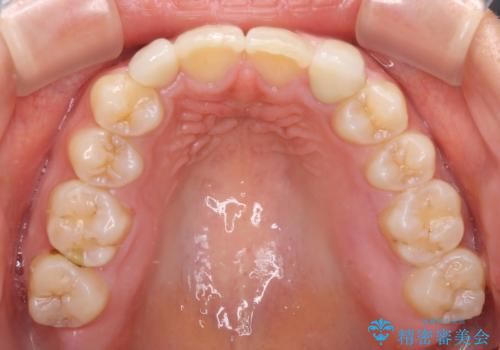

矯正治療の段階で、矮小歯は前後にスペースが作ってあったため、極力左右対称の歯冠形態となるように補綴治療を行うこととしました。

歯根の太さや幅が左右で異なるため、歯肉ラインはどうしても左右非対称となってしまいますが、とても自然な口元となりました。